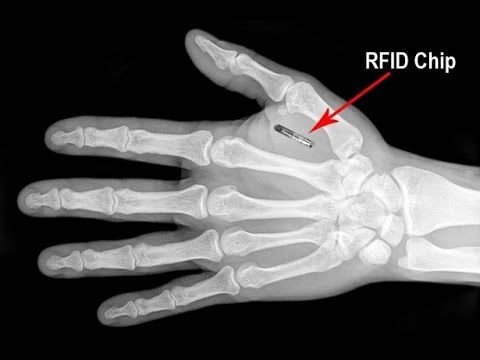

>人口削減計画とか5Gとかマイクロチップ

都市伝説でただの噂ならどれだけいいかね。

まぁあなたは10年後気づいてよ、手遅れだろうけど。+15